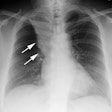

Bronchiolitis obliterans:

The patient shown below had experienced a severe right lower lobe haemophilus influenza pneumonia the preceding year, but had persistent pulmonary complains. The inspiratory CT images reveal bronchiectatic changes involving the bronchi to the anterior and medial basal segments of the right lower lobe (yellow arrows). Expiratory images deomstrate air trapping in these same segments (white arrows). Air trapping is also evident in the medial segment of the right middle lobe. The findings are consistent with post-infectious bronchiolitis obliterans.